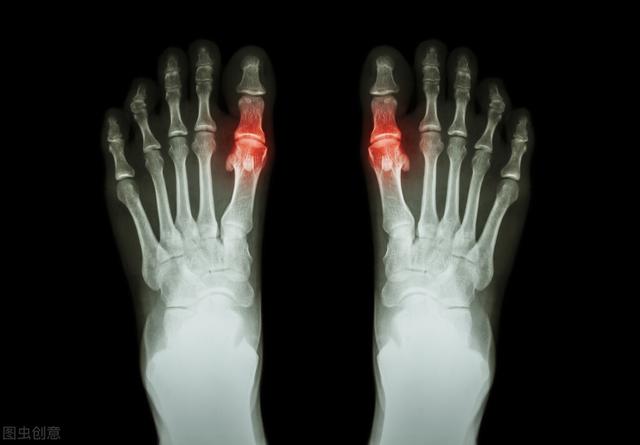

La détermination de la goutte dépend principalement des articulations. Au début de l'apparition de la goutte, 53 % à 70 % des patients ont les articulations du premier orteil (appelées goutte du pied) rouges, gonflées, chaudes et douloureuses, généralement multiples, certaines pouvant aussi se manifester sous forme d'articulations multiples. Elle est fixe et asymétrique, et peut progressivement envahir des articulations plus importantes telles que les chevilles, les genoux, les poignets et les coudes.

La deuxième étape consiste à effectuer une étude d'imagerie, par exemple pour détecter un "signe de double piste" sur l'échographie ou pour effectuer un "signe de double piste" sur l'échographie.La tomodensitométrie à double énergie révèle des dépôts d'urateetc., puis ouLes radiographies révèlent un gonflement des tissus mous, une destruction des bords du cartilage et une irrégularité des surfaces articulaires.!

La goutte peut être détectée par imagerie, la présence de cartilage articulaire "signe de double piste", l'épanchement articulaire, l'érosion osseuse, etc., peuvent également être diagnostiqués par des indicateurs de la fonction rénale.

- (10) Tuméfaction intra-articulaire asymétrique (confirmée par radiographie)

- (11) Kyste sous-cortical de l'os sans érosion osseuse (confirmé par radiographie)